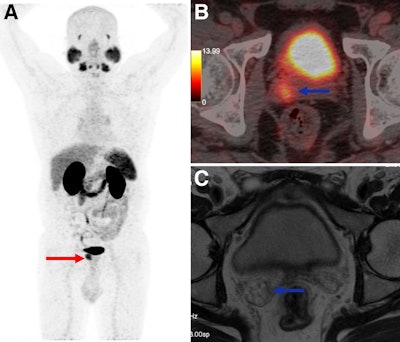

A 55-year-old man presenting for initial staging of prostate cancer. (A) Ga-68 PSMA-11 PET/CT maximum-intensity projection shows PSMA-expressing lesion involving prostate (red arrow), with PSMA avidity in right seminal vesicle invasion (blue arrow). (B) PET/CT axial image shows right seminal vesicle invasion (blue arrow). (C) However, MRI at same topography shows no seminal vesicle invasion. Pathology analysis confirmed Ga-68 PSMA-11 PET/CT-positive results.Journal of Nuclear Medicine